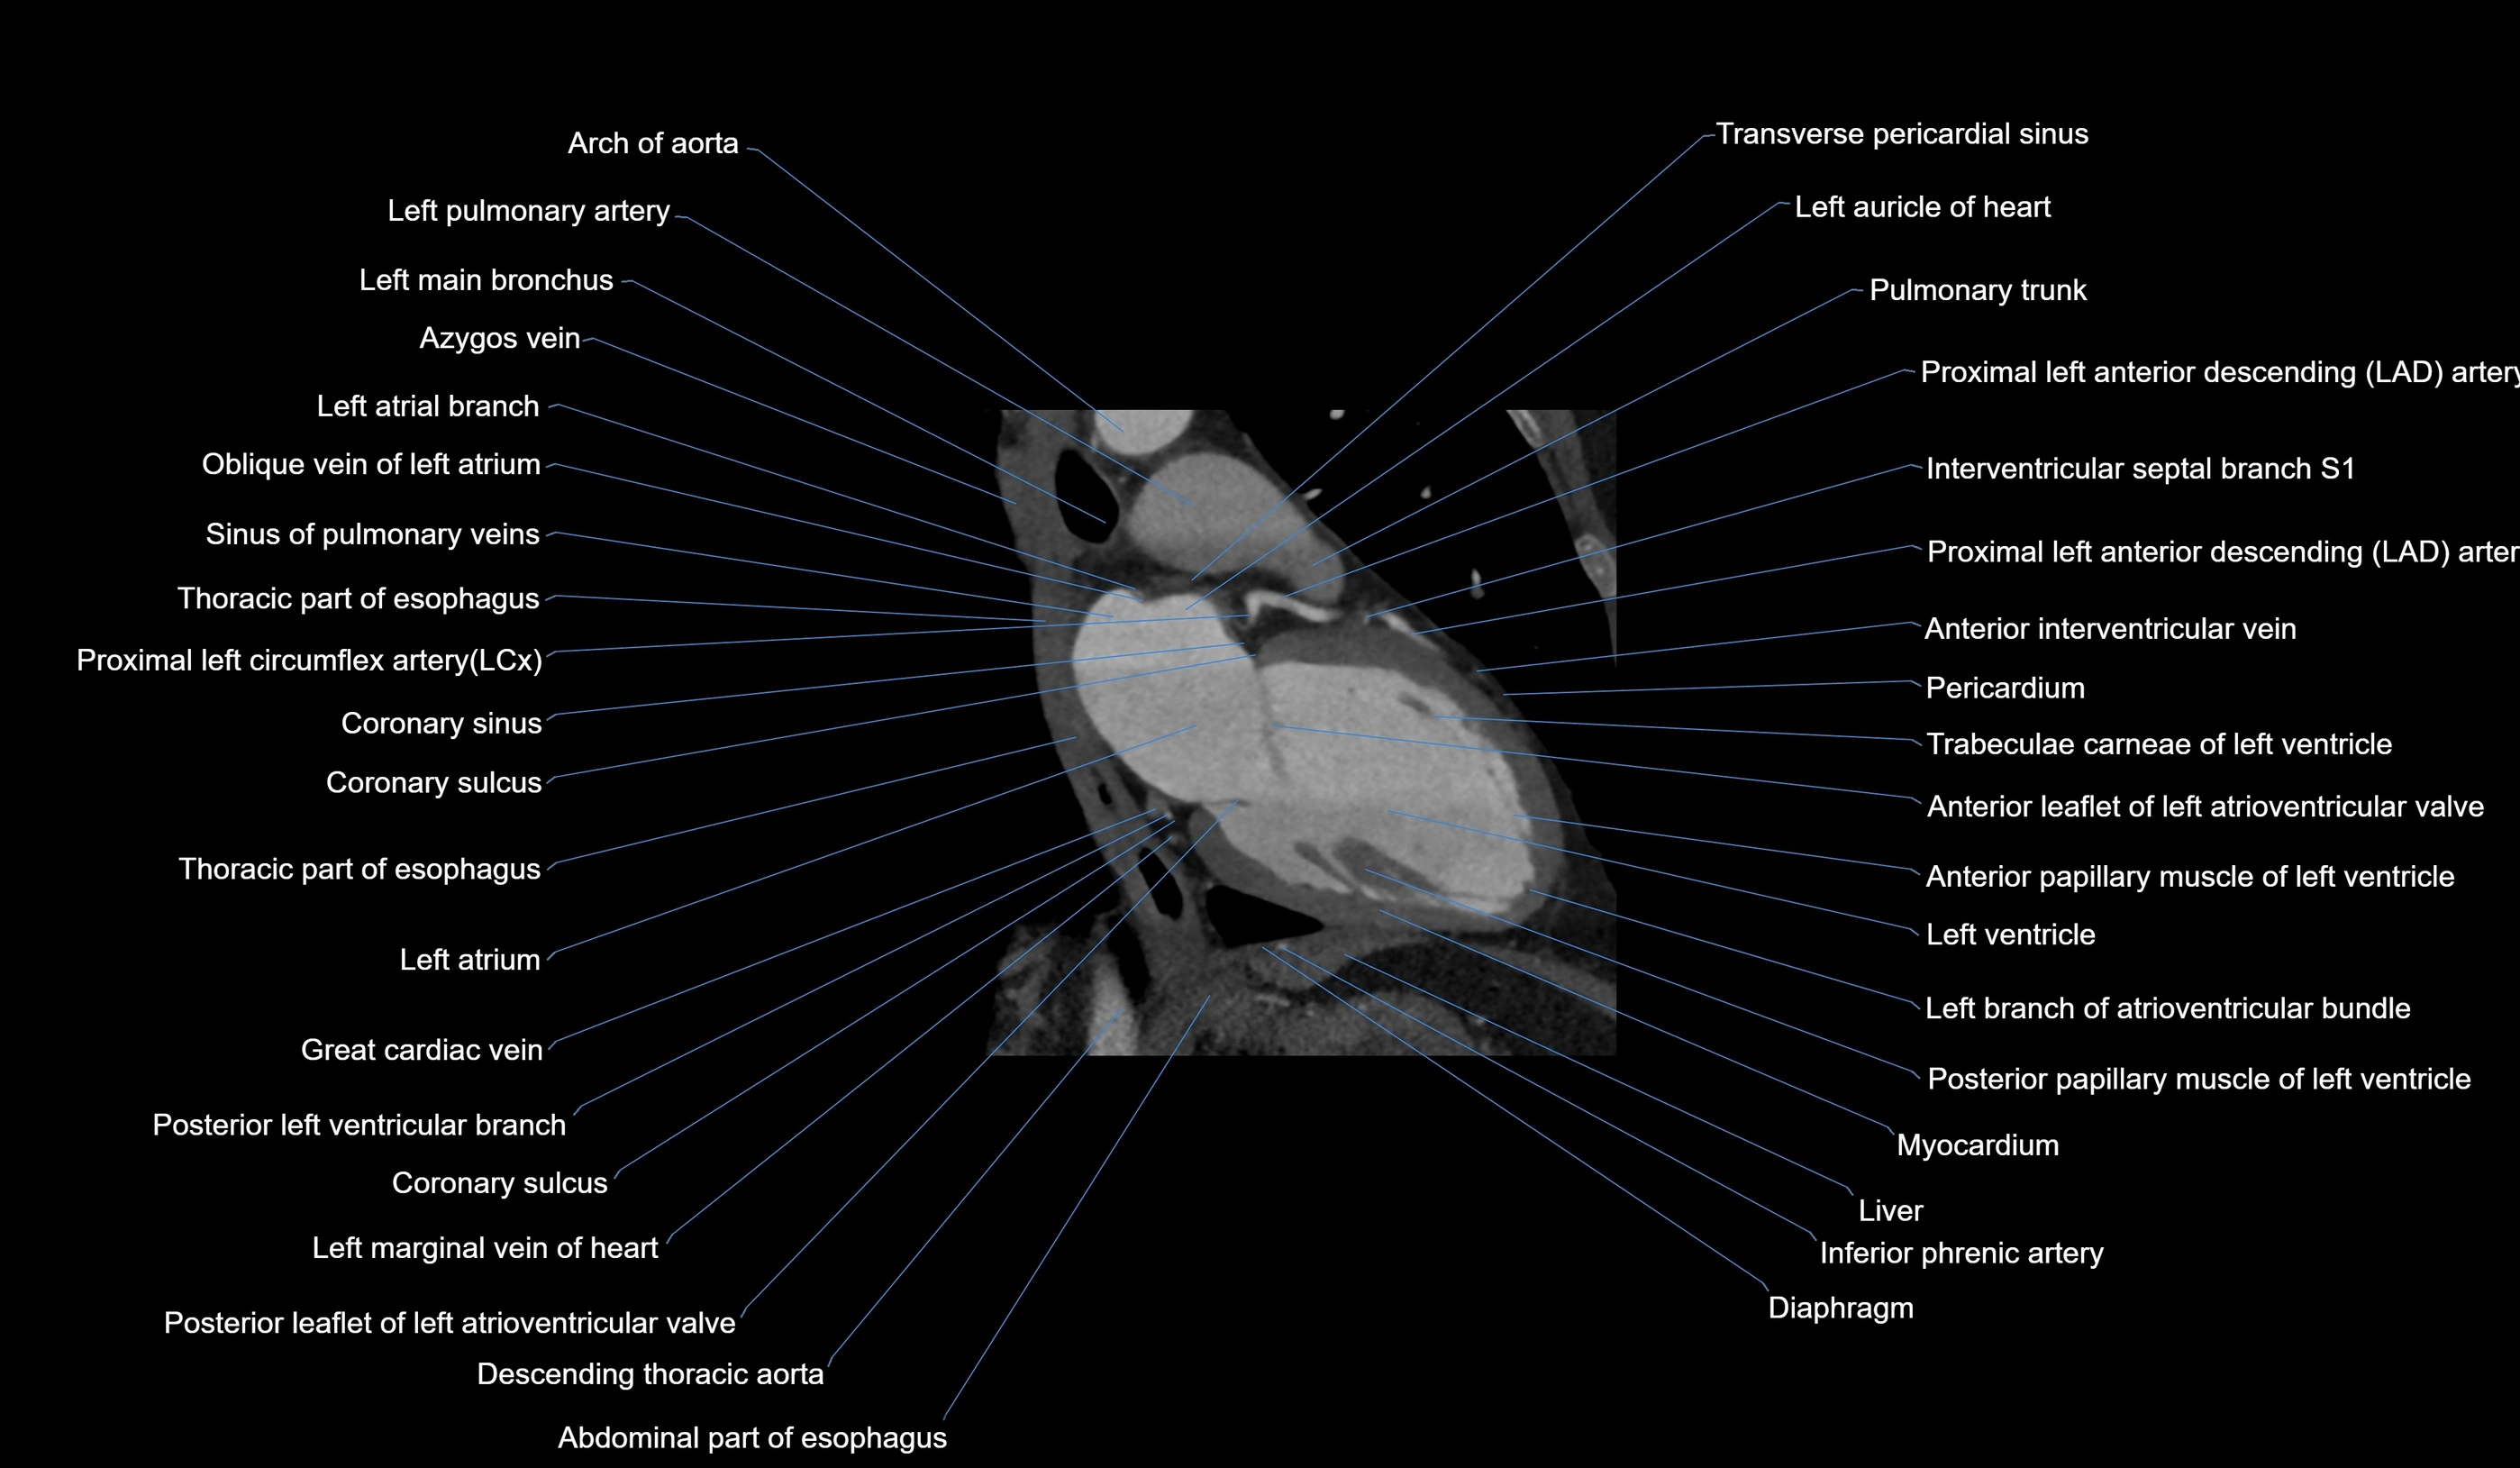

- Acute marginal artery (AM)

CT Appearance

CT Coronary Angiography (CCTA):

-

Best non-invasive modality for acute marginal artery visualization

Shows origin, course along the acute margin, and right ventricular branches

Detects stenosis, occlusion, calcified and non-calcified plaques, aneurysm, or anomalous course

Multiplanar reformats and 3D reconstructions help in pre-PCI and surgical planning

Critical for assessing right ventricular infarction risk in RCA disease

MRI image

CT images